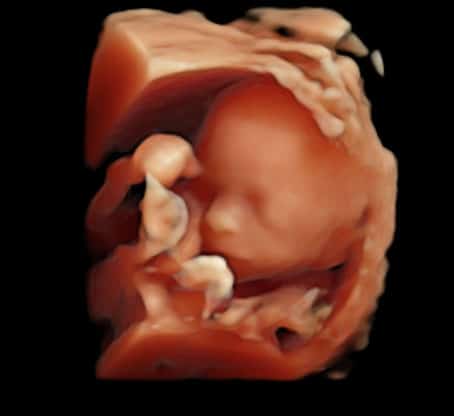

3. L’échographie du 2ᵉ trimestre (22 à 23 SA – 4mois 1/2)

Souvent appelée échographie morphologique, elle est dédiée à l’étude détaillée de l’anatomie fœtale.

Elle permet :

• D’examiner tous les organes du bébé : cerveau, cœur, reins, estomac, membres, colonne vertébrale, etc.

• D’évaluer la croissance et le bien-être fœtal

• De repérer certaines malformations si elles sont présentes

• De contrôler la position du placenta et la quantité de liquide amniotique

C’est aussi, si vous le souhaitez, le moment de découvrir le sexe du bébé.

Selon la position du bébé, nous vous proposons une échographie en 3D.